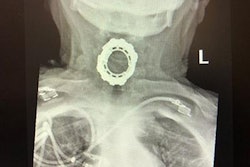

When they cut into the cyst, they discovered the mandibular-like structure and eight teeth. They tried cutting and removing the mandibular-like bone with traditional gynecologic techniques using surgical scissors and a scalpel, but it posed the risk of damaging the instruments and failed to remove the specimen, the authors noted.

Lab results revealed that the cyst contained hair, fat, cartilage, and teeth, and the histological appearance of the jaw-like structure was mature bone, according to the report.